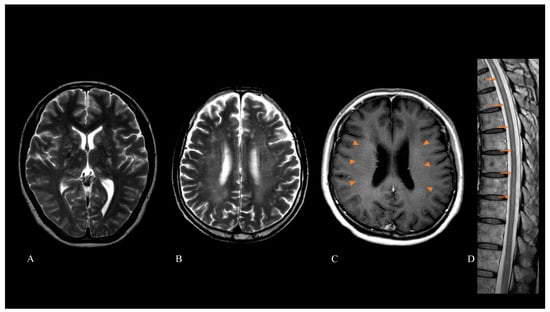

| Brain MRI findings | ||

| T2/FLAIR hyperintensity lesions | 76/86 (88) | |

| Hyperintensities in white matter | 49/84 (58) | |

| Hyperintensities in basal ganglia | 36/84 (43) | |

| Hyperintensities in cerebellum | 5/84 (6) | |

| Gadolinium enhancement lesions | 53/78 (68) | |

| LPRGE patterns | 42/78 (54) | |

| Spinal cord MRI findings | ||

| Intramedullary T2 hyperintensity lesions | 29/71 (41) | |

| Gadolinium enhancement lesions | 24/51 (47) | |

| Intramedullary enhancement lesions | 12/51 (24) | |

| Meningeal enhancement lesions | 13/51 (25) | |